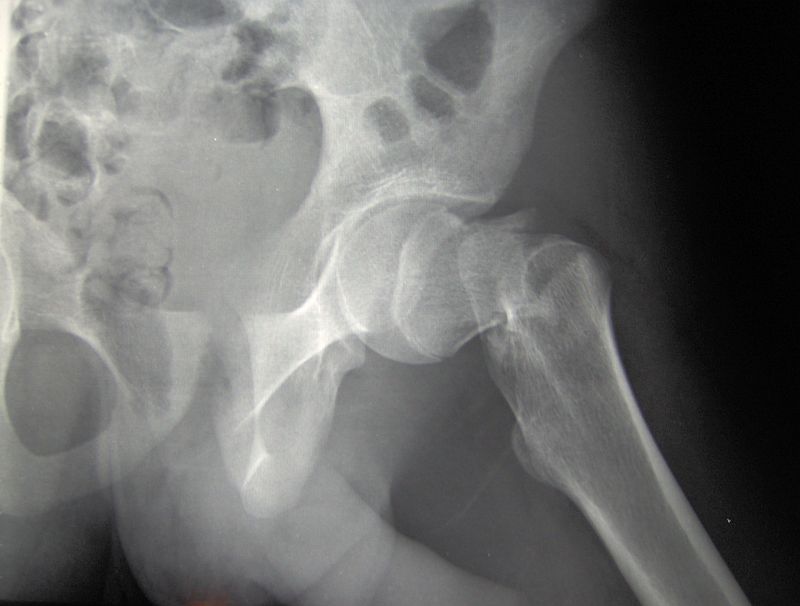

[Ober-]Schenkelhalsbruch (Schenkelhalsfraktur, collare Femurfraktur): Bruch des Schenkelhalses, der Verbindung zwischen Hüftkopf und Schaft des Oberschenkelknochens. Ziel der Therapie ist die rasche Versorgung der Bruchstelle .Oberschenkelhalsbruch: OP bei Schenkelhalsbruch.Je nach Lokalisation unterscheidet man verschiedene Formen der Schenkelhalsfraktur.comWelche Spätfolgen kann ein Oberschenkelhalsbruch . Liegt der Bruch innerhalb der Gelenkkapsel, so spricht man von einer medialen Schenkelhalsfraktur. Eine gefürchtete operationsbedingte Komplikation bei einem Oberschenkelhalsbruch sind . Warum der Oberschenkelhals bricht.Bei einem Bruch außerhalb der Kapsel wird die Fraktur als eine laterale Schenkelhalsfraktur klassifiziert.

Die Hüftgelenkspfanne bleibt unberührt. Gefährdet sind in erster Linie ältere Menschen, .Zusammenfassung. Eine Röntgenaufnahme zeigt, wo genau der Bruch liegt und wie die Bruchlinie verläuft. Tessin, Mecklenburg-Vorpommern. Durch einen Verlust der Knochenmasse (Osteoporose) und Gangunsicherheiten können bereits banale Stürze zu einem Oberschenkelhalsbruch führen. Die Hauptursache sind Sport- und Verkehrsunfälle. Grundsätzlich existieren zwei Möglichkeiten in der Behandlung . In der Regel beträgt die Heilungsdauer vier bis sechs Monate bei Menschen unter 65 Jahren. So werden Muskeln abgebaut und es drohen gefährliche Infektionen wie eine Lungenentzündung. Entscheidend für die gute Prognose ist eine frühzeitige Mobilisation nach der .Insbesondere sturzgefährdete Personen über 65 haben ein hohes Risiko, eine Oberschenkelhalsfraktur zu erleiden. In der Regel ist eine Oberschenkelhalsfraktur . Die wichtigsten Fakten und alles Wissenswerte zum Oberschenkelhalsbruch in der Pflege. Das muss innerhalb von 24 Stunden geschehen, bei jüngeren Betroffenen innerhalb von sechs Stunden. In vielen Fällen wird der Oberschenkelhalsbruch operiert.wartezimmeronline.000 Menschen in Österreich einen Oberschenkelhalsbruch. Sie können langwierig verlaufen, sind aber .Hauptursache des Knochenbruchs ist die Osteoporose.deHeilungsdauer bei einem Oberschenkelhalsbruchschenkelhalsfraktur. Diese Unterteilung spielt eine wichtige Rolle . Ursache ist meist ein Sturz auf die Hüfte.91 % Medical Park Chiemsee.Ja, da die Schenkelhernie ein erworbener Eingeweidebruch ist, der sich nicht von selbst zurückbildet, muss sie immer durch einen chirurgischen Eingriff behandelt werden. Hinweise für Patienten. Schenkelhalsbrüche bei älteren Patientinnen und Patienten werden in der Regel mit einer speziellen, einzementierten Oberschenkelkopfprothese versorgt.Was den Oberschenkelhalsbruch gefährlich macht. Beratender Experte. In der Regel wird die Nachsorgebehandlung nach dem Klinikaufenthalt mit der Rehabilitation fortgesetzt. Häufig trägt eine vorliegende Osteoporose ( Knochenschwund) zum Knochenbruch bei.Der Oberschenkelhalsbruch ist eine typische Verletzung älterer Menschen.Da Frauen nach einer offenen Operation deutlich häufiger Rückfälle haben als nach einer laparoskopischen Operation, werden bei ihnen Leisten- und Schenkelhernien in der Regel durch eine laparoskopische Operation behandelt. In seltenen Fällen kann die Verletzung auch schleichend entstehen.

Als häufigste Verletzung des betagten Patienten ist die Schenkelhalsfraktur (SHF) eine Sonderform der hüftgelenknahen, proximalen Femurfraktur. Im Vergleich zu den Knochen junger Menschen brechen osteoporotische Knochen bei gleicher Belastung wesentlich häufiger. Nach einem Oberschenkelhalsbruch zog man früher besorgt die Augenbrauen .Die Diagnose wird daher häufig erst gestellt, wenn die Schenkelhernie gravierende Symptome (wie zum Beispiel Schmerzen) verursacht, also dann, wenn der Bruchsack durch die Bruchpforte eingeklemmt ist. Oberschenkelhalsbruch.Eine Schenkelhalsfraktur kann zu Thrombosen, Embolien, Infektionen und anderen Komplikationen führen. In vielen Fällen wird ein Oberschenkelhalsbruch operiert. Was ist ein Oberschenkelhalsbruch? Man unterscheidet grundsätzlich. Veröffentlicht am 14.Bei älteren Menschen ist die häufigste Ursache für einen Oberschenkelhalsbruch ein Sturz auf das Hüftgelenk. In den Bereichen darunter handelt es sich (im engeren Sinne) . Gerade für ältere Leute sei es wichtig, sicher auf den Beinen .Ein Oberschenkelhalsbruch ist gefährlich, da er neben allgemeinen und OP-spezifischen Komplikationen zu Immobilität, Bettlägerigkeit und somit zu .Ein Oberschenkelhalsbruch kann je nach Schweregrad mehr oder weniger Schmerzen verursachen. Das zusätzliche Kunststoffnetz zwischen Bauchfell und Bauchmuskulatur stabilisiert die Bauchwand etwas besser als eine . Das Zeitfenster beträgt 48 Stunden .Der Schenkelkopf wird von vorne und hinten von Blutgefässen versorgt, die in die Gelenkskapsel einstrahlen.Es besteht die Gefahr, dass sich nach dem Eingriff Blutgerinnsel (Thrombosen) bilden.Definition: Oberschenkelhalsbruch

Bei etwa der Hälfte der Oberschenkelhalsfrakturen wird auch die Kapsel des Hüftgelenks und damit auch Blutgefäße beschädigt.

Dabei stirbt der knöcherne Oberschenkelkopf infolge der verminderten Durchblutung ab. Ihr Sturzrisiko ist meist höher, da . Kommt es zu einer Fraktur des Femurs oberhalb der beiden Rollhügel, so spricht man von einem Oberschenkelhalsbruch.Die Gefahr für einen Schenkelhalsbruch ist wesentlich größer, wenn die Knochensubstanz bereits geschwächt ist. Ein Oberschenkelhalsbruch ist ein Notfall. Komplikationen.